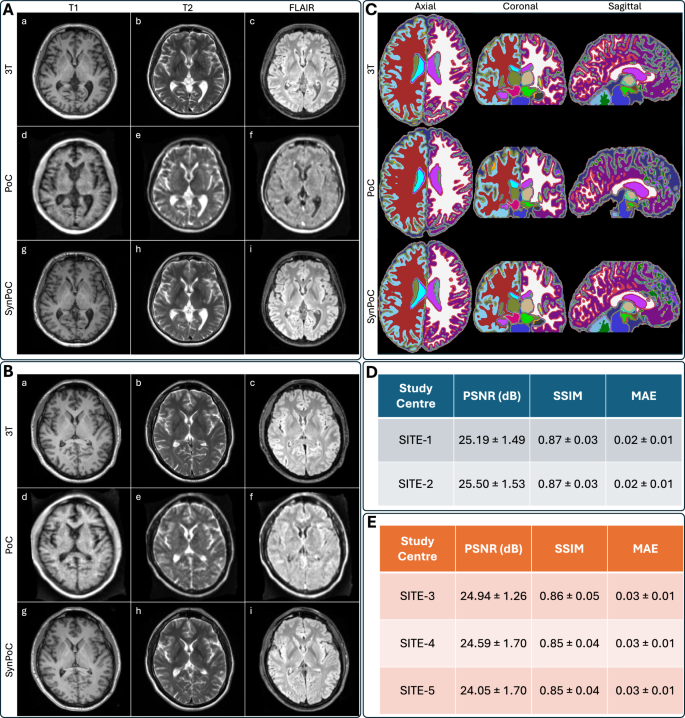

Figure 2 presents qualitative and quantitative comparisons of MRI modalities across different sites, including brain parcellation and performance metrics for both healthy and clinical participants. SynPoC demonstrates notable improvements in visual clarity, anatomical detail, and resemblance to high-field MRI images. Figure 2A illustrates the image output of the SynPoC model applied to ULF MRI data from a healthy participant at SITE-1. Whereas the ULF T1-weighted MRI images exhibit limited anatomy in the cortical gyration and deep gray nuclei, these features appear markedly improved in the synthetic SynPoC images, though some fine structures may still differ from true high-field anatomy. Similarly, ULF FLAIR images show significantly lower contrast between gray and white matter, making it difficult to distinguish these regions. SynPoC enhances the contrast, yielding FLAIR images with improved differentiation between gray and white matter that more closely resembles high-field MRI, albeit with subtle alterations in contrast representation. Across all sequences, the ventricular Cerebrospinal fluid (CSF) spaces appear larger at ULF than the reference 3T, which is visually adjusted by SynPoC toward 3T-like appearance. Visual resemblance between SynPoC and 3T is also observed in extracranial structures such as the skull and scalp. Similar results are achieved from SITE-2, Figure 2B, which is noteworthy as this center did not contribute data to the training model. Brain parcellations using the SynthSeg\({^+}\)53 and the MGH-subcortical atlas, as shown in Fig. 2C, indicate that SynPoC-generated images support improved structural delineation of subcortical anatomy, showing high similarity to 3T images in appearance.

Quantitative image metrics and inter-site variability

Commonly used image quality metrics, including Peak Signal-to-Noise Ratio (PSNR), Structural Similarity Index Measurement (SSIM), and Mean Absolute Error (MAE) for SynPoC images versus the high-field reference for the healthy group datasets, highlighting how the model adjusts ULF image characteristics to better resemble high-field representations, are shown in Fig. 2D54. While these metrics offer a quantitative perspective on image similarity, they are inherently limited in capturing clinical relevance or perceptual quality, as highlighted in previous studies55. To address this, we additionally assessed volumetric consistency in brain regions commonly examined in neuroimaging studies. Data from SITE-1, used for primary model development, and SITE-2 showed no statistically significant between-site difference in any of PSNR (t = −0.80, p = 0.430), SSIM (t = 0.00, p = 1.000), or MAE (t = 0.00, p = 1.000), with no statistically significant differences in structural similarity metrics. These quality metrics also remained consistent across clinical sites, SITE-3 to SITE-5, in patients with various clinical imaging scenarios (Fig. 2E). Data from SITE-3, SITE-4, and SITE-5 showed no statistically significant differences in PSNR or SSIM between sites. The marginal differences in the quantitative metrics between healthy and clinical sites are likely attributed to the domain shifts due to clinical image features.

Qualitative and quantitative results from different MRI modalities across imaging sites and healthy and clinical participants. (A) Results for a healthy male participant in his early 60s from imaging site SITE-1. (a)–(c) represent 3T T1, T2, and FLAIR sequences, (d)–(f) show corresponding PoC sequences, and (g)–(i) illustrate SynPoC images. (B) Results for a healthy female participant in her late 40s from imaging site SITE-2 (Herston Imaging Research Facility). (a)–(c) represent 3T T1, T2, and FLAIR sequences, (d)–(f) show corresponding PoC sequences, and (g)–(i) illustrate SynPoC images. (C) Brain parcellation volumes across different MRI modalities from imaging site SITE-1 (male, late 30s). Each column represents a different view in axial, coronal, and sagittal orientations, with rows corresponding to the respective MRI modalities. (D) Quantitative performance metrics (PSNR, SSIM, MAE) for healthy data from SITE-1 and SITE-2. (E) Quantitative performance metrics for clinical data from SITE-3, SITE-4, and SITE-5.